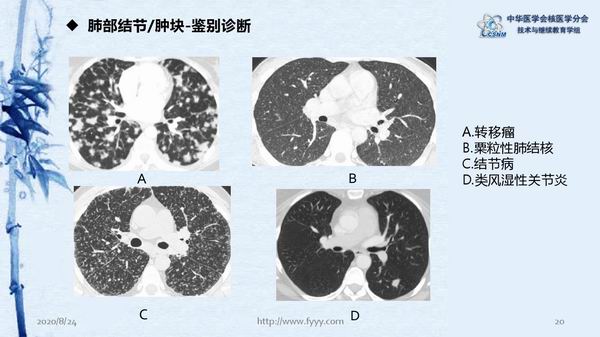

病例82:肉芽肿性血管炎PET-CT显像一例-【CSNM继教学组】郑山 福建医科大学附属第一医院